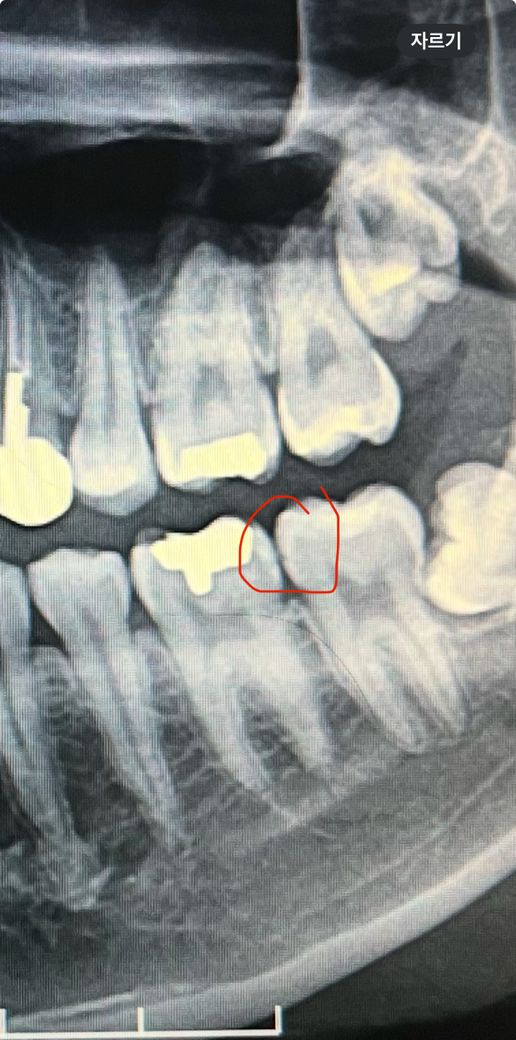

이 엑스레이 사진 사이충치인지 알려주세요

치과에서 저 부분 검진받고 엑스레이 찍고 보셨을때 별 문제 없고 충치는 따로 없다고 하시는데 이게 충치인지 모르겠네요.. 제가 항상 치실로 관리하는 부분인데 의사임께서 어둡다고 무조건 충치는 아니고 혹시 충치이더라도 두고 보는게 나을 것 같다고 하시네요 저걸 확인하는게 더 손해라고 하십니다 저 부분이 충치가 맞을까요?

치아 사이에 충치가 조금은 잇는거 같습니다. 충치가 많이 진행된건 아니니 일단은 관리하시면서 지켜보셔야될것같습니다.

현재 사진 상에서는 충치의 양상으로 보이지는 않습니다. 지켜보면서 관리 잘하는 게 최선같습니다.

충치가 의심되긴 하는데 저정도 충치 치료하려고 위에서부터 뚫고 내려가면 더 손해일 수도 있습니다 특별히 증상 없으면 관리 잘하고 지켜보는것도 방법입니다

사진으로만 봤을 경우에는 에나멜의 표면이 약해지는 형태를 보이는것 같습니다.

하지만 정확한 확인을 위해서는 좀더 지켜봐야 해아 할것으로 생각됩니다.